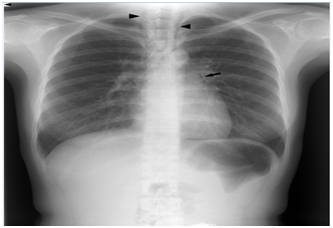

A previously healthy 28-year-old woman suddenly developed left chest pain while eating lunch, with no cough or vomiting. She visited my office because of persistent chest pain and anxiety. Her vital signs were stable on admission. She had not taken any medications recently, nor reported a habit of cigarette smoking. Physical examination revealed no aerodermectasia or abnormal chest sounds, including crunching heart sounds. The electrocardiogram (ECG) was normal. Chest radiographs showed air dissecting the left second arc protrusion Figure 1, black arrow and in the superior mediastinum Figure 1, black arrow head. Computed tomography (CT) of the chest also revealed air in the mediastinum Figure 2, white arrow, as well as aerodermectasia Figure 2, arrow head not detected in the radiographs, without pneumothorax or oesophageal rupture. An oesophagogram demonstrated no leakage in the mediastinum or pleural space. These findings confirmed a diagnosis of SPM. The patient’s chest pain improved gradually, and spontaneously resolved completely within 1 week with conservative management.

Figure 1 A chest radiograph showing intramediastinal air.